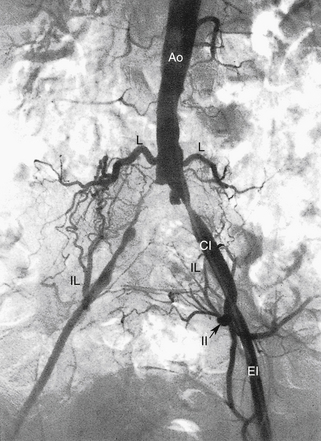

РИСУНОК 13-9. А. Брюшная аорта (Ао) заканчивается разветвлением на общие подвздошные артерии (CI) на уровне позвонка L4. Б. Общие подвздошные артерии делятся в пояснично-крестцовом соединении на внутреннюю (II) и наружную подвздошную (EI) артерии. Внутренняя подвздошная артерия (также называемая подчревной артерией) снабжает внутренние органы и мускулатуру таза. Ветви этой артерии становятся важными сопутствующими путями, как видно на других рисунках. Наружная подвздошная артерия переходит в общую бедренную артерию у паховой связки, как показано на рисунке 13-10 . C : Трехмерная объемная (VR) компьютерная томографическая (КТ) ангиограмма аорты и сегмента подвздошно-бедренной артерии. D. Проекция максимальной интенсивности (MIP) КТ-ангиограммы подвздошно-бедренных сегментов демонстрирует очаговые кальцификации в открытых сосудах. E — магнитно-резонансная ангиограмма (МРА) с усилением гадолинием аорты, подвздошного и бедренного сегментов. Анатомия наглядно иллюстрируется методами трехмерной реконструкции. С, чревная артерия; H, печеночная артерия; НМА, нижняя брыжеечная артерия; R, левая почечная артерия; рРГ – замена правой печеночной артерии; S, селезеночная артерия; СМА, верхняя брыжеечная артерия.